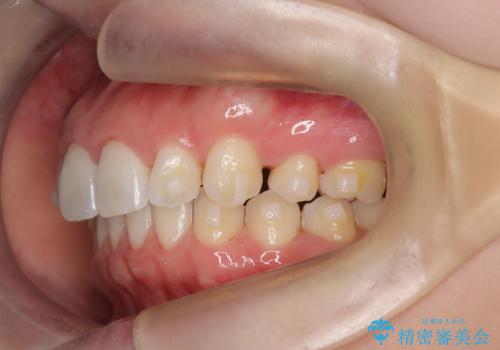

- 患者様は、上下顎の歯列不正と前歯部の突出感を主訴としてご来院されました。診断の結果、上顎左右第一小臼歯を抜歯することでスペースを確保し、歯列全体を整える方針としました。本来はワイヤー矯正が推奨されるケースですが、患者様のご希望により、透明なマウスピース型矯正装置「インビザライン」を使用した治療計画を立案しました。治療期間は約3年で、奥歯の噛み合わせを維持しながら、徐々に前歯の位置を整えました。

インビザラインは見た目の目立ちにくさと取り外しが可能な点がメリットですが、複雑なケースでは治療計画の精密さが求められます。本症例では奥歯の噛み合わせが崩れないよう注意を払いながら、マウスピースの交換タイミングを細かく設定しました。患者様には装着時間を守っていただくことが重要で、1日20時間以上の装着が必須です。また、抜歯部位のスペースを閉じる過程で、歯の動きが停滞しやすい時期もあるため、定期的なチェックを通じて治療が順調に進むよう管理しました。